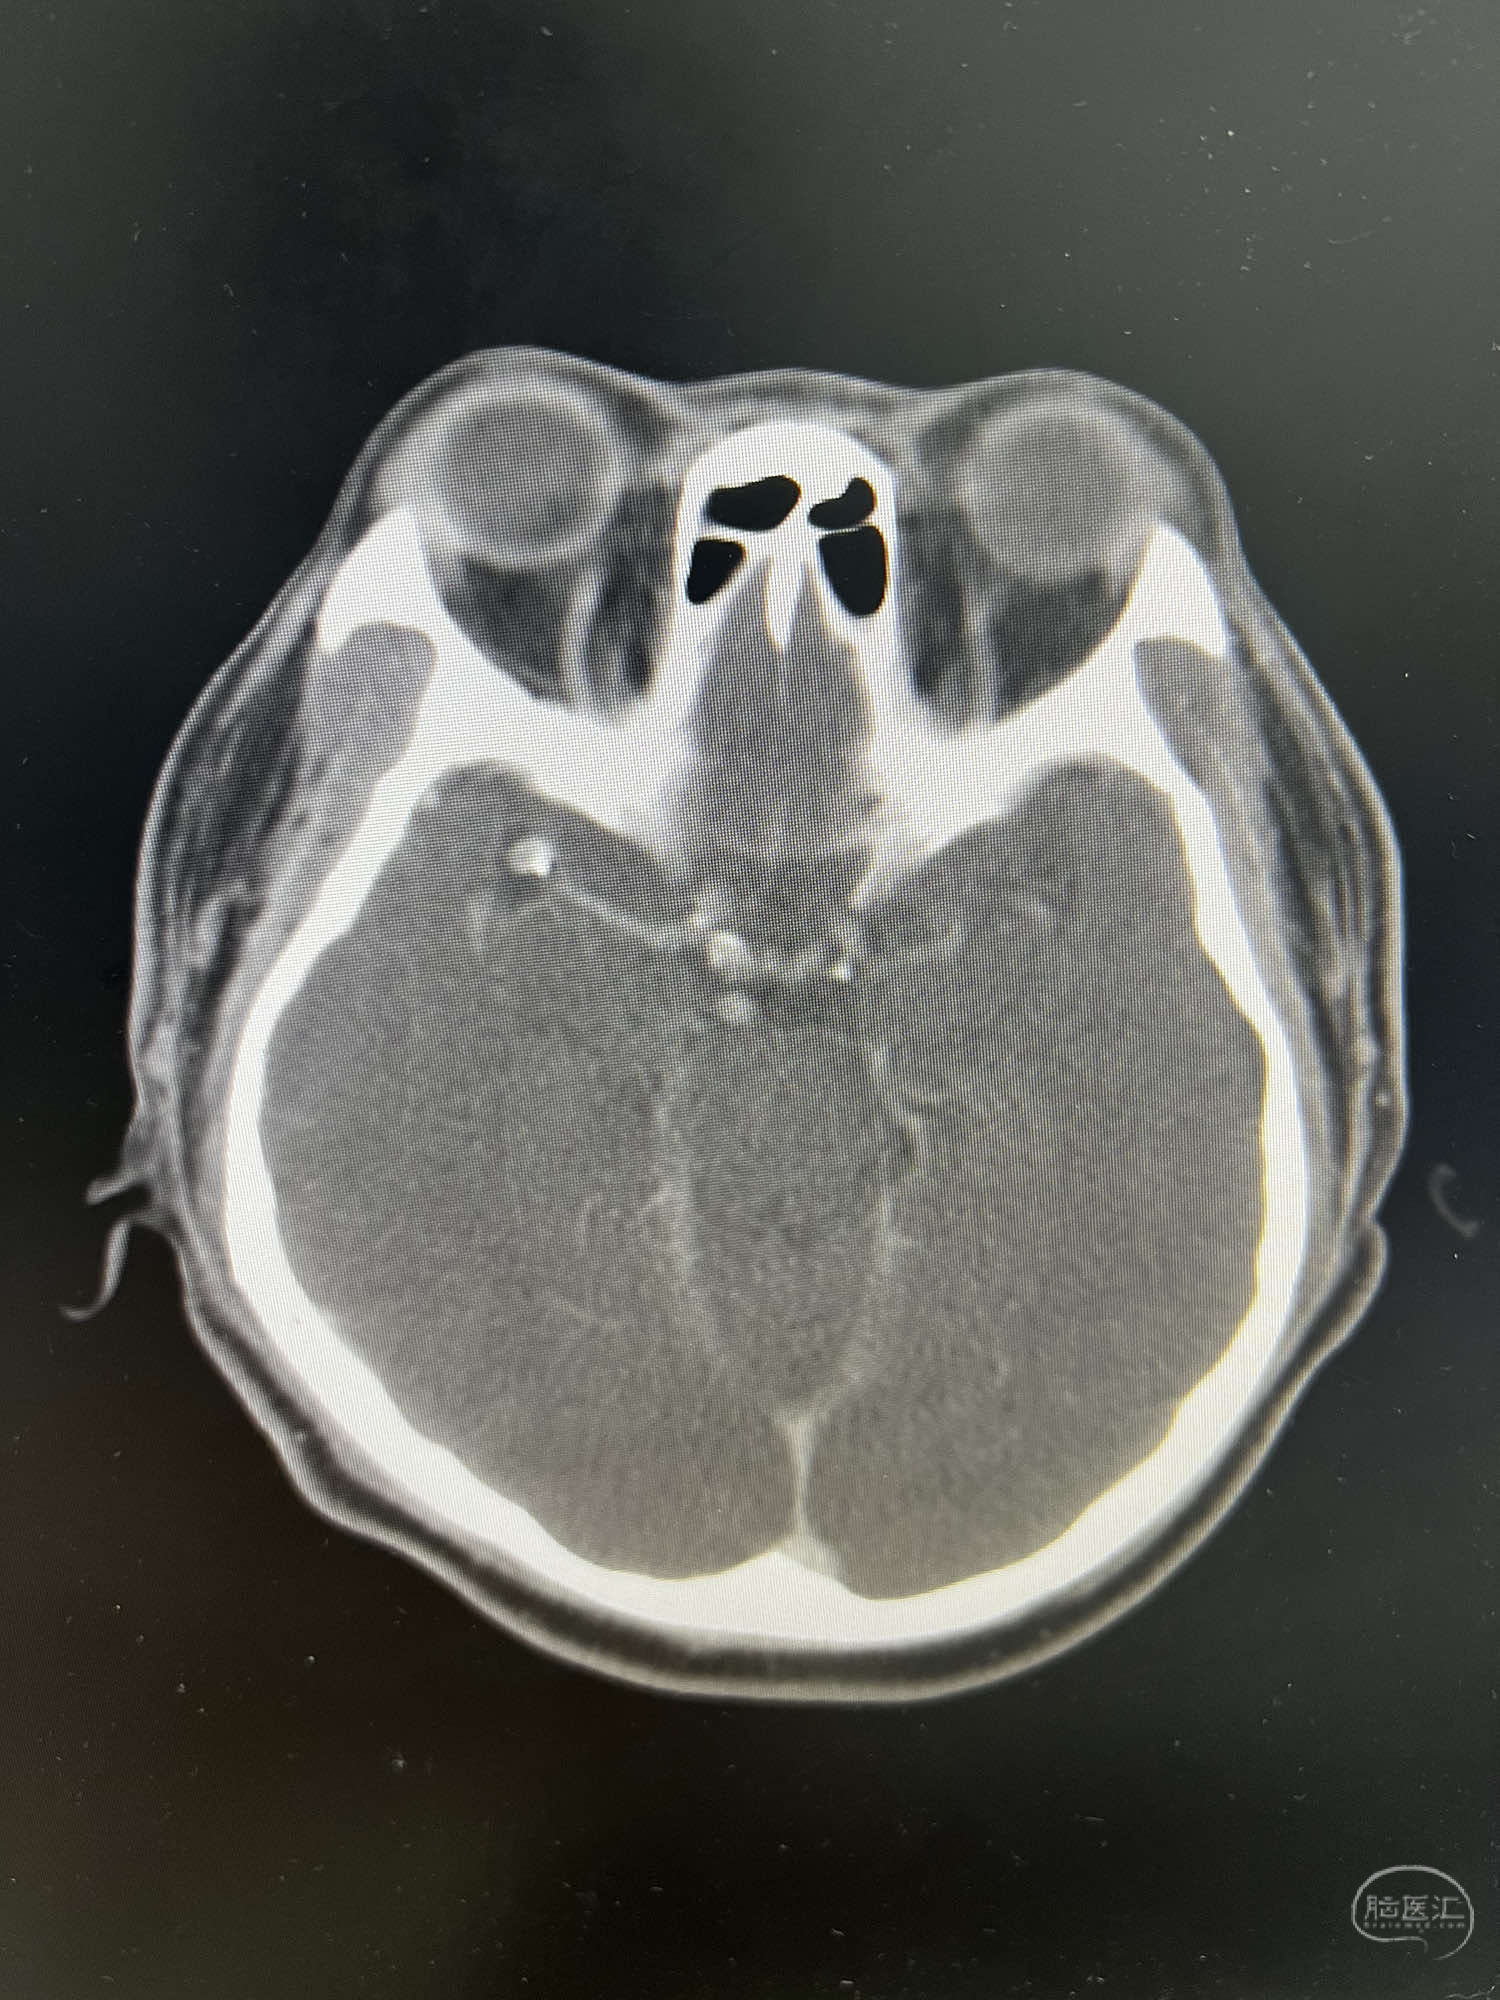

患者:LXS,M53Y,以“间断头晕头痛1周”为主诉入院,既往有高血压病及长期吸烟史。在当地医院行头颅CT未见异常,头颅MRA示右侧大脑中动脉M1段末端动脉瘤,左侧颈内动脉闭塞,交通动脉开放。